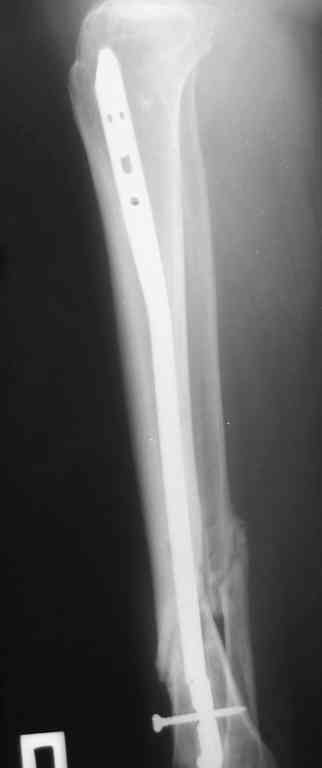

Прилагаются.

Да , обсуждалась и оптимальным штифтом был выбран " Мастер" Остеомед 10 мм и винты 5 мм, но увы все наши благие намерения разбились о нашу действительность и материальные возможности больной, обращение ее в страховую компанию и т.д., вообщем выкручивались из внутренних резервов, а они были такими 9 мм штифт Остеомед, под 4 мм винты. Ограничили нагрузку. Ошиблись еще и с оценкой сращения, дали полную нагрузку+ больная поправилась на 18 кг, и вот теперь имеем , что имеем.

Действитльность и возвожности остались прежнее, во внутренних резервах есть 11 мм стержень универсальный ( реконструктивный) "Деост-CHM" много спиц и аппарат + ось конечности и отломок штифта и надежда на Ваши советы.